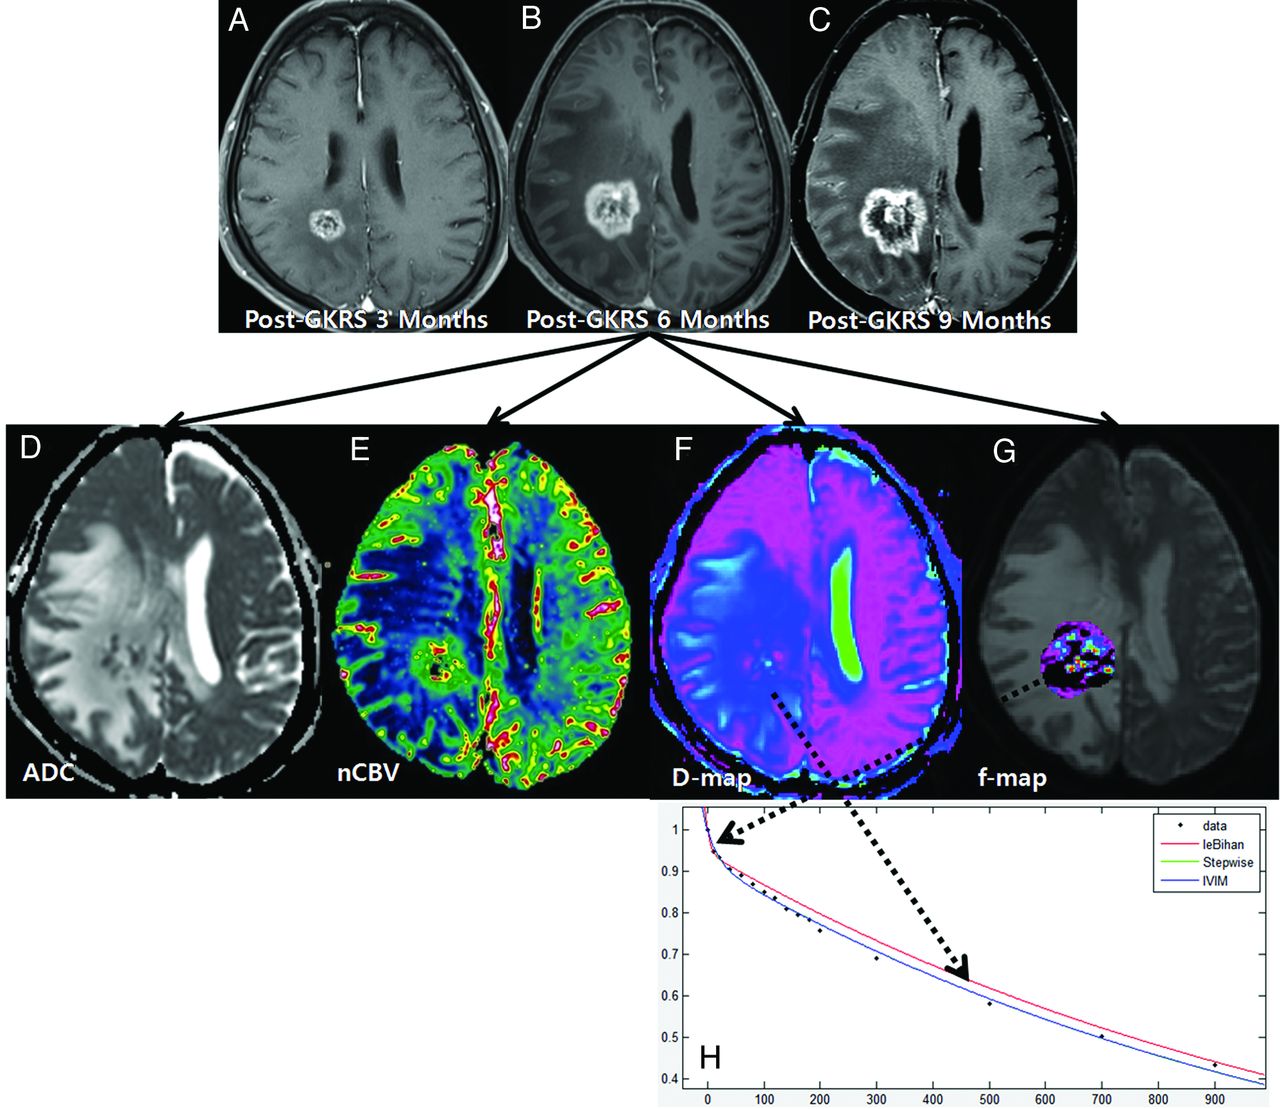

A 61-year-old woman with treatment effect following GKRS. Axial contrast-enhanced T1-weighted images, obtained 3 (A) and 6 months (B) after GKRS, show a progressively enlarging necrotic contrast-enhancing lesion in the left parietal lobe. C, The necrotic contrast-enhancing lesion is stabilized on a subsequent follow-up image obtained 9 months after GKRS, thus indicating treatment effect. The ADC (D) and nCBV (E) maps show no visual decrease of the ADC and no visual increase of the nCBV in the corresponding area of the contrast-enhancing lesion in B, respectively. The D (F) and f (G) maps show no visual decrease of the D value and no visual increase of the f value in the corresponding area of the contrast-enhancing lesion in B, respectively. H, The signal decay curve, plotted as a function of the diffusion b-values, is monoexponential.

Among the 91 study patients, analysis of all of the patients with recurrent tumor and 9 patients with treatment effect showed that the signal decay curve, plotted as a function of the diffusion b-values, was biexponential and ranged from 0 to 900 s/mm2. The recurrent tumor group showed more rapid signal decay than the treatment effect group in the range of lower b-values (b < 200 s/mm2) (Fig 3). In the remaining 43 patients with treatment effect, the signal decay curve was similar to the monoexponential pattern (Fig 2). The f, nCBV, D, and ADC maps of representative cases of recurrent tumor and treatment effect are shown in Figs 2 and 3.